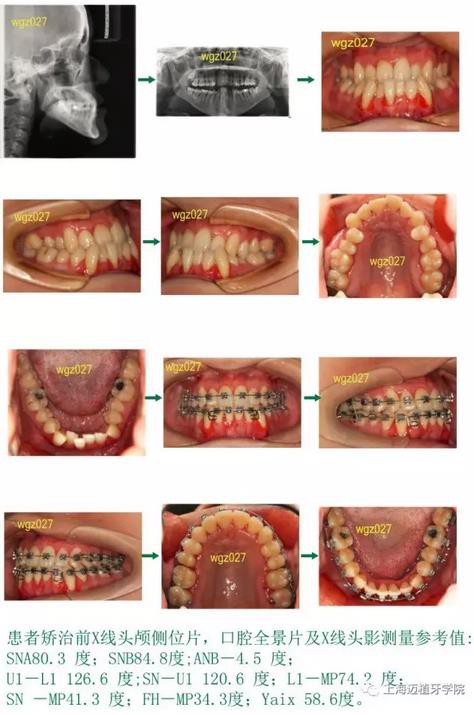

【歷史培訓(xùn) 病例展示】